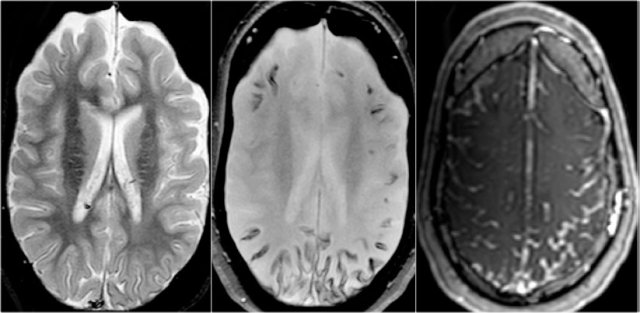

Coronal T2W and FLAIR images are the most sensitive for detecting MTS.

On axial slices mesial temporal sclerosis is commonly overlooked.

The coronal T2WI and FLAIR images show right-sided mesial temporal sclerosis.

Notice the volume loss, which indicates atrophy and causes secondary enlargement of the temporal horn of the lateral ventricle.

The high signal in the hippocamous reflects gliosis.

The images show mesial temporal sclerosis with a hyperintense and shrunken hippocampus (red arrows), and secondary enlargement of the left temporal horn of the left laterale ventricle.

Also notice associated subcortical hyperintensity in the left temporal lobe indicating focal cortical dysplasia.